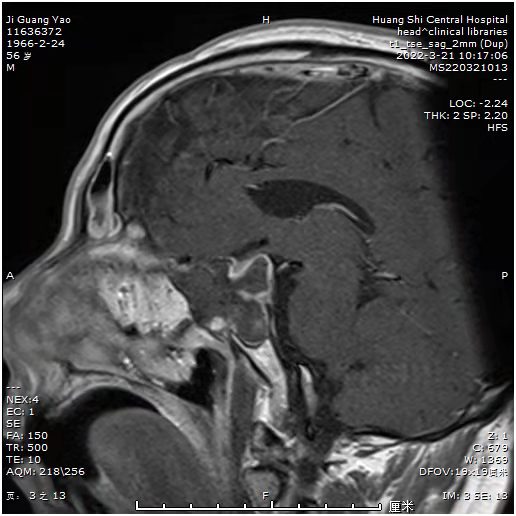

术中的情况。可见肿瘤藏在各个条索状分隔里,分离分隔。吸除肿瘤,尽量清除条索样物。可见鞍膈下降。术后患者诉视力明显改善。眼睛暴胀感消失。

术后显示肿瘤切除满意,正常垂体及垂体后叶后叶保留,术后患者诉视力明显改善。眼睛暴胀感消失。视力基本正常范围。